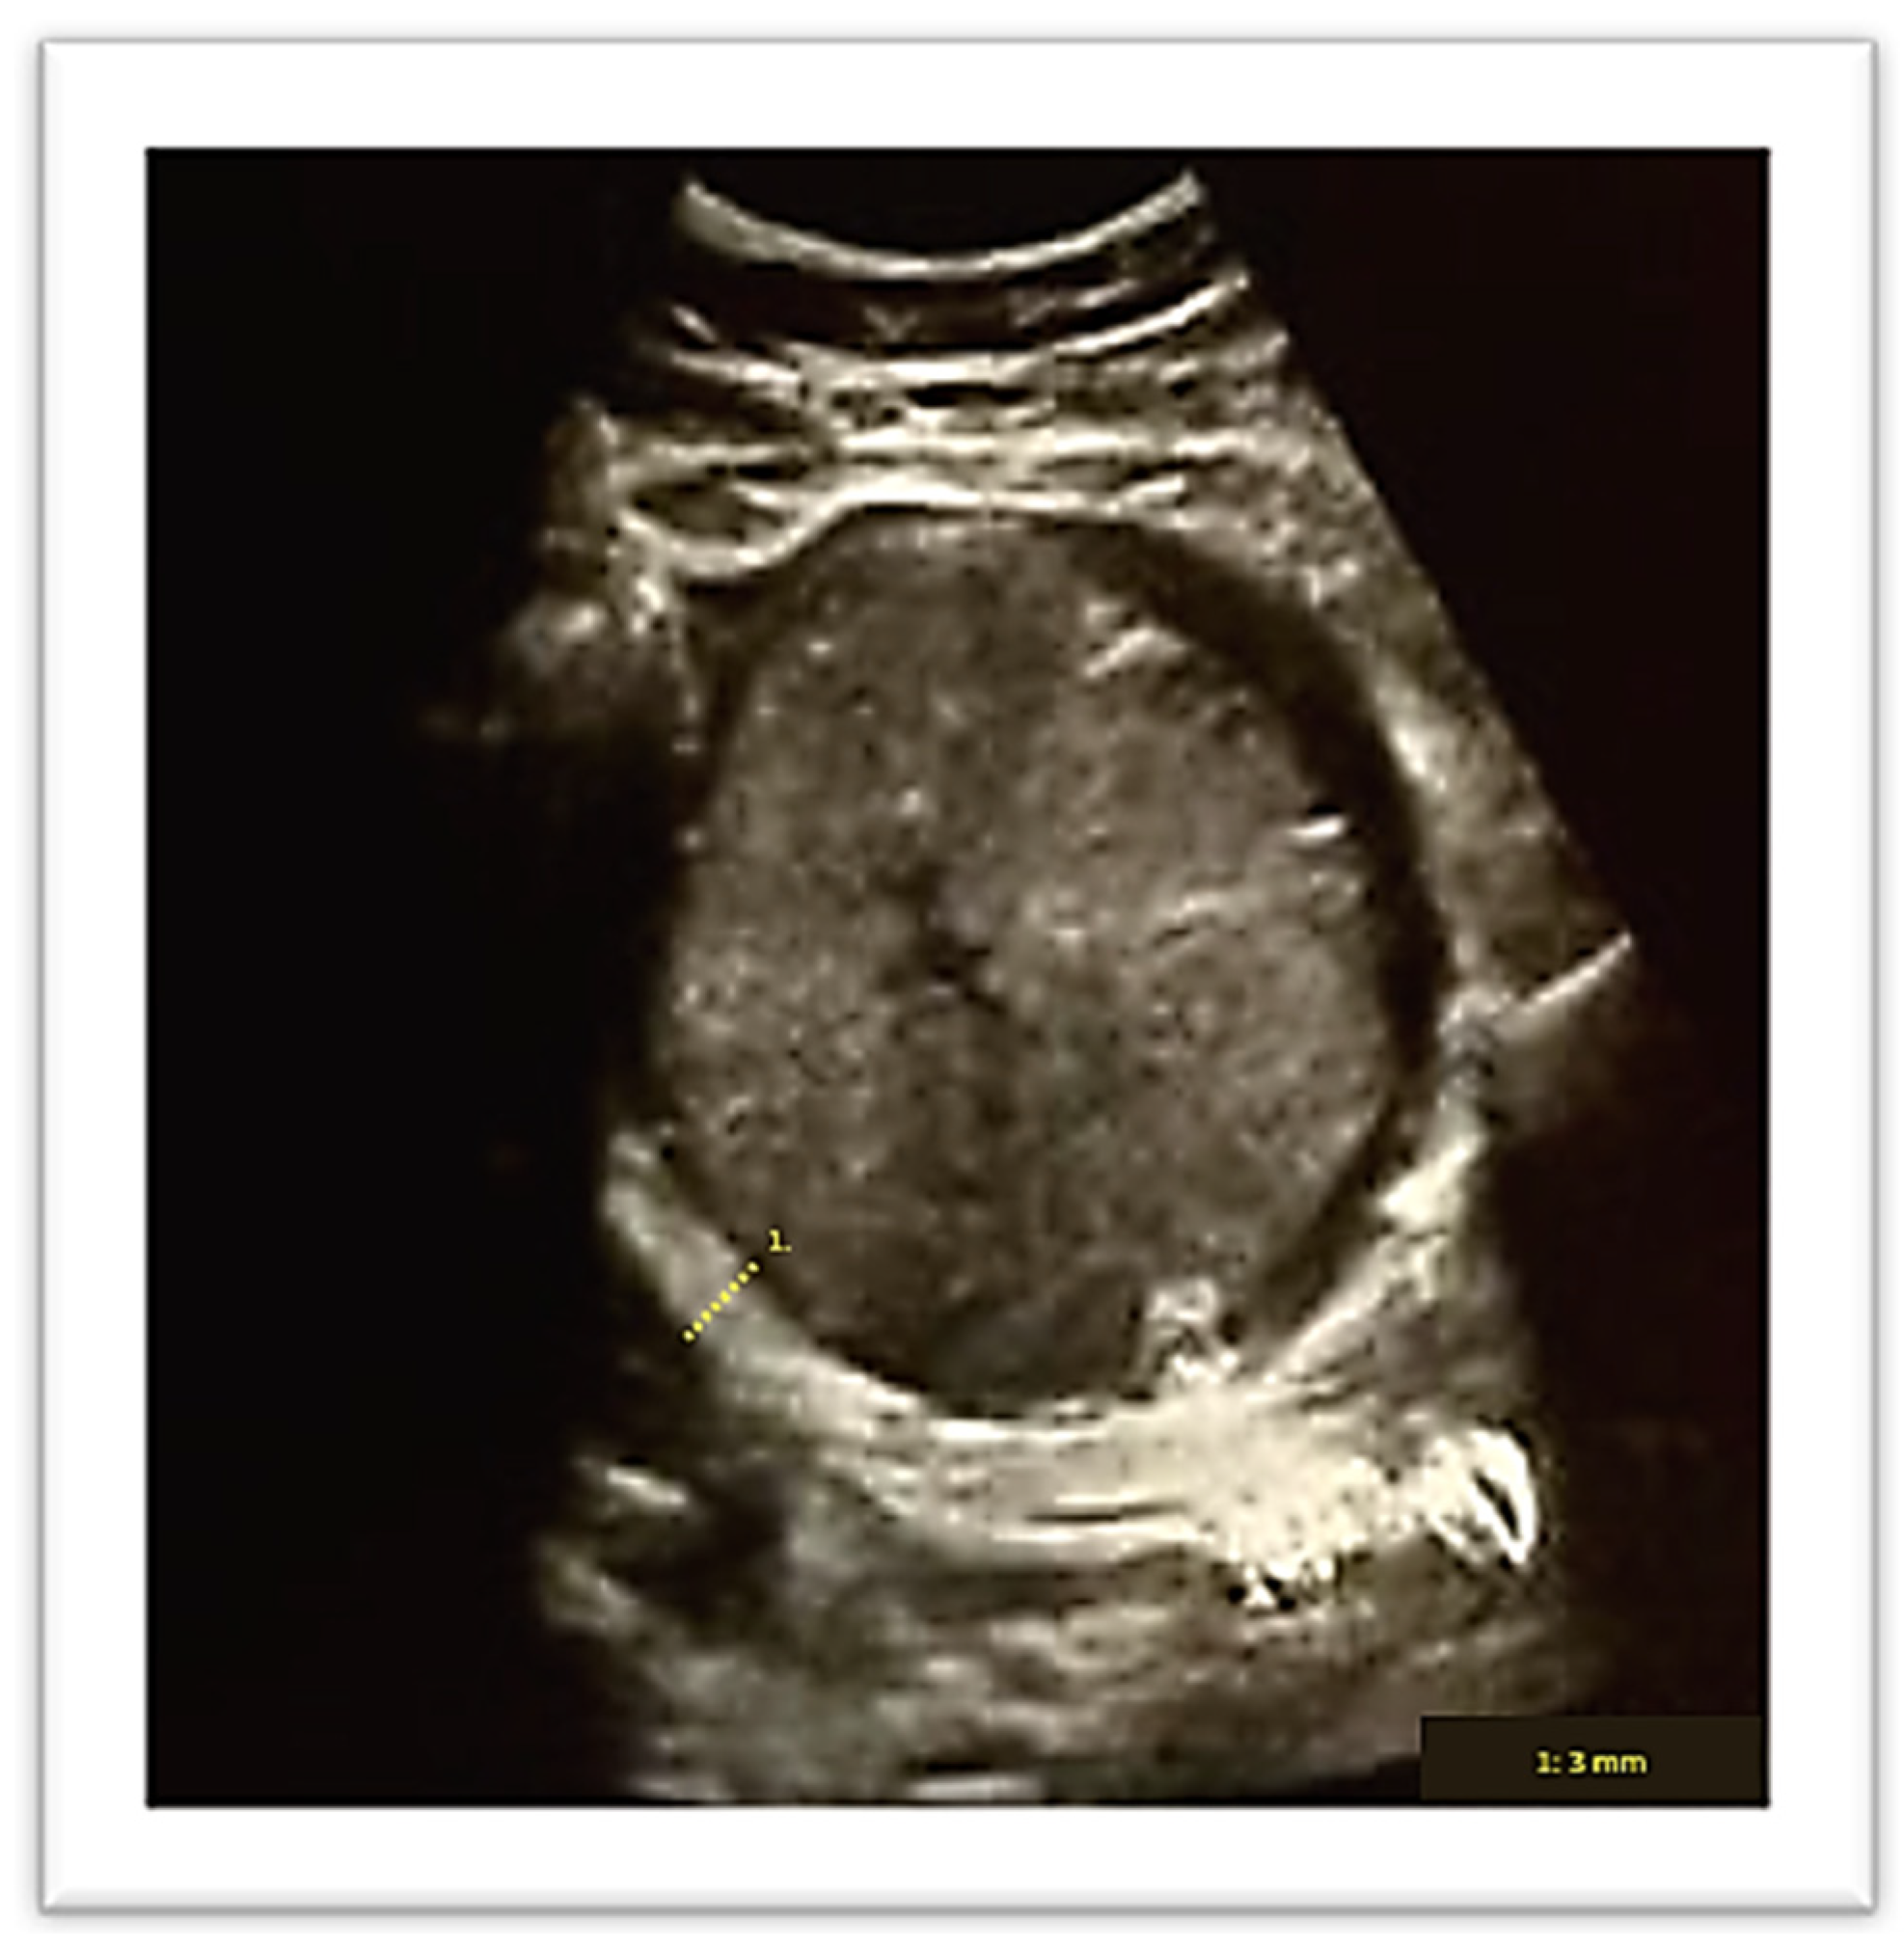

2. Case Report

4.1. Angular Pregnancy Diagnosis